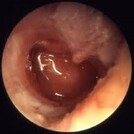

A clinical examination typically involves looking into the ear with an otoscope to assess the appearance of the eardrum and presence of fluid. Understanding the patient's history of symptoms such as ear pain, fever, and recent respiratory infections is also crucial.